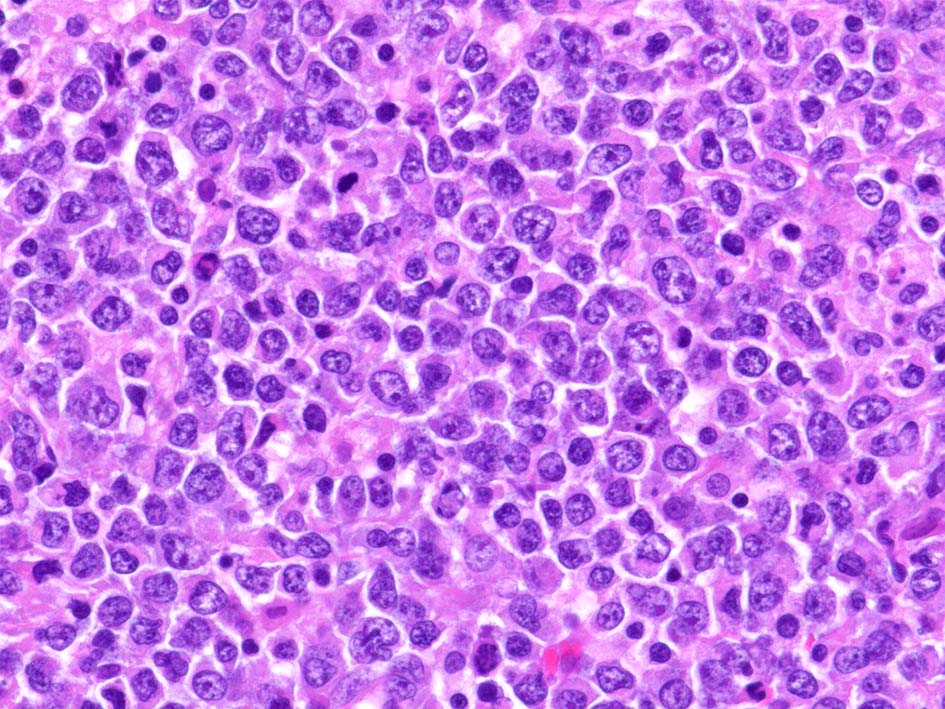

精細管の多くがスペアされ, 間質にlymphoid cellsが密に浸潤している. わずかな精細管に浸潤が認められ萎縮や破壊像が認められる. 精細管において Lymphoepithelial lesion(LEL)に似た所見がある.

類円形/多稜形の核をもつN/C比大の細胞. 粗大なクロマチンが増加, 核小体は不明瞭. DLBCLに認められるcentroblasts/ immunoblastsの細胞所見と異なる.

LCA(CD45)+, CD20+(focalに陰性), CD79a+, PAX5+, CD5-, CD10+, BCL6+が多い, MUM1-, BCL2+, cyclinD1-, MIB1 LI; very high(>80%). EBER-ISH-.

IGH; clonal band+ (BIOMED2, FR1 and FR2). MYD88L265PはAS-specific PCRで陰性. Molecular にもcommon typeのtesticular DLBCLとは異なっているようである.